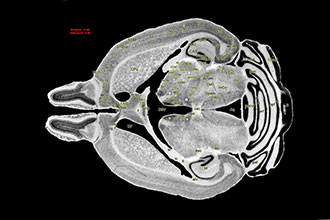

据英国《自然》杂志近日发表的一项研究,日本科学家使用一种名为CUBIC-X的技术绘制了一张小鼠大脑图谱,该技术不但使组织像玻璃一样透明清楚,还可将其膨胀至其原始尺寸的十倍。这一新成果为人类窥探生物系统的内部运作,提供了前所未有的机会。

而此次,日本RIKEN生物系统动力学研究中心的上田泰己带领团队,采用化学方法标记了大脑中的每个细胞,将大脑“透明化”,并与此同时将其尺寸扩大了10倍。研究团队还利用精密成像技术对神经元进行三维重建,总计约7200万个细胞。他们所得的图谱,将大脑缩小为一个简洁的细胞位置数据库,可以研究不同大脑区域的具体变化。

研究人员表示,这类方法的应用正不断扩展,CUBIC-X技术是其中之一。这类技术可以对生物体组织进行清除,使原本不透明的组织变透明;还可以在清除组织的同时将器官按比例放大,让更多细节暴露在传统显微镜下。其利用现成的化学物质为科学家们打开了一扇大门,让人们不仅可以观察大脑,还可以观察其他任何一个器官。